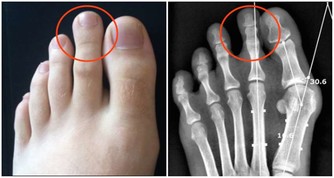

線索五:羅圈腿

預警:骨關節炎

整形外科專家認為這種步態通常是由於膝關節炎造成的,人群中有高達85%的人或多或少患有這種骨科疾病,通常是由於年齡增長造成骨骼損耗引起的,如果嚴重,可通過支架糾正。

線索六:內八字

預警:風濕性關節炎

這種炎症會造成內八字的步態,有85%的風濕性關節炎患者會表現出這種特徵。它在醫學上被稱為膝外翻或者外翻足,表現為小腿無法伸直,向外側彎曲。這種步態非常與眾不同,看上去笨拙,雙膝併攏在一起,而踝關節外翻。